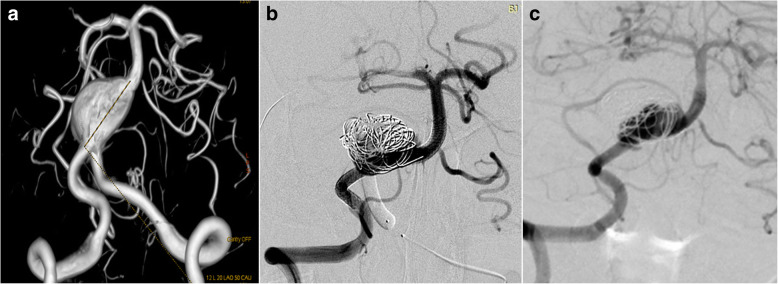

This was a 61 years old female presented with a ruptured PCoA aneurysm which incorporated the origin of a right fetal PCA. The aneurysm was measured 3.0 mm*4.0 mm with a relative wide neck and two daughter aneurysms (Fig. 1a). We postponed the procedure 20 days after the onset of SAH to avoid the potential risks of dual antiplatelet therapy. The daughter aneurysm located superiorly was considered to be the rupture point, so we first loosely embolised it with three coils measured 2 mm*3 cm, 1.5 mm*2 cm, 2 mm*4 cm, then we deployed a 4.5 mm*20 mm PED from M1 segment to supraclinoidal segment of ICA covering the neck of the aneurysm (Fig. 1b). No further coiling of the aneurysm was performed in consideration of the future patency of fetal PCA. The follow up angiogram on 4 months demonstrated the patency of the fetal PCA and the aneurysm has slightly decreased in size (Fig. 1c), however there remained contrast agent filling in the aneurysm sac. Note that the right A1 is no longer patent and the patient was asymptomatic due to the compensatory flow from the AComA (Fig. 1d). So we discontinued the dual antiplatelet therapy and leave this patient on MRI follow up, we will not retreat the patient unless the patient will present with headache and enlargement of the aneurysm on MRI image.

Fig. 1.

3D DSA image of Case NO. 1 before the treatment (a), immediate postoperative angiogram (b) and on follow-up (c), note that the right A1 was not patent, the distal part of right ACA was supplied by compensatory flow from the AComA (d)